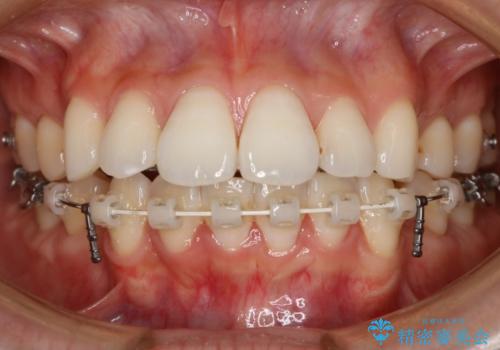

- ワイヤー(片顎舌側装置)

- 治療計画

ハーフリンガル装置

ハーフリンガルとは上顎を裏側、下顎を表側のワイヤー装置で治療する場合をいいます。